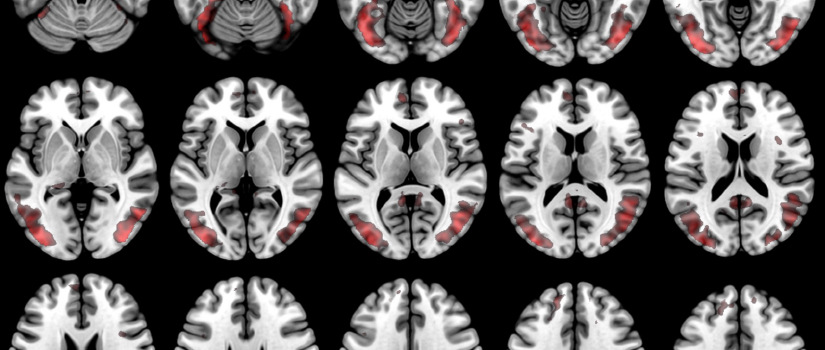

The Siemens 3-Tesla Magnetic Resonance Imaging system at the McCausland Center is state-of-the-art equipment which allows researchers to understand how the healthy brain works. In addition, this system provides an important tool for understanding brain injury and guiding rehabilitation.